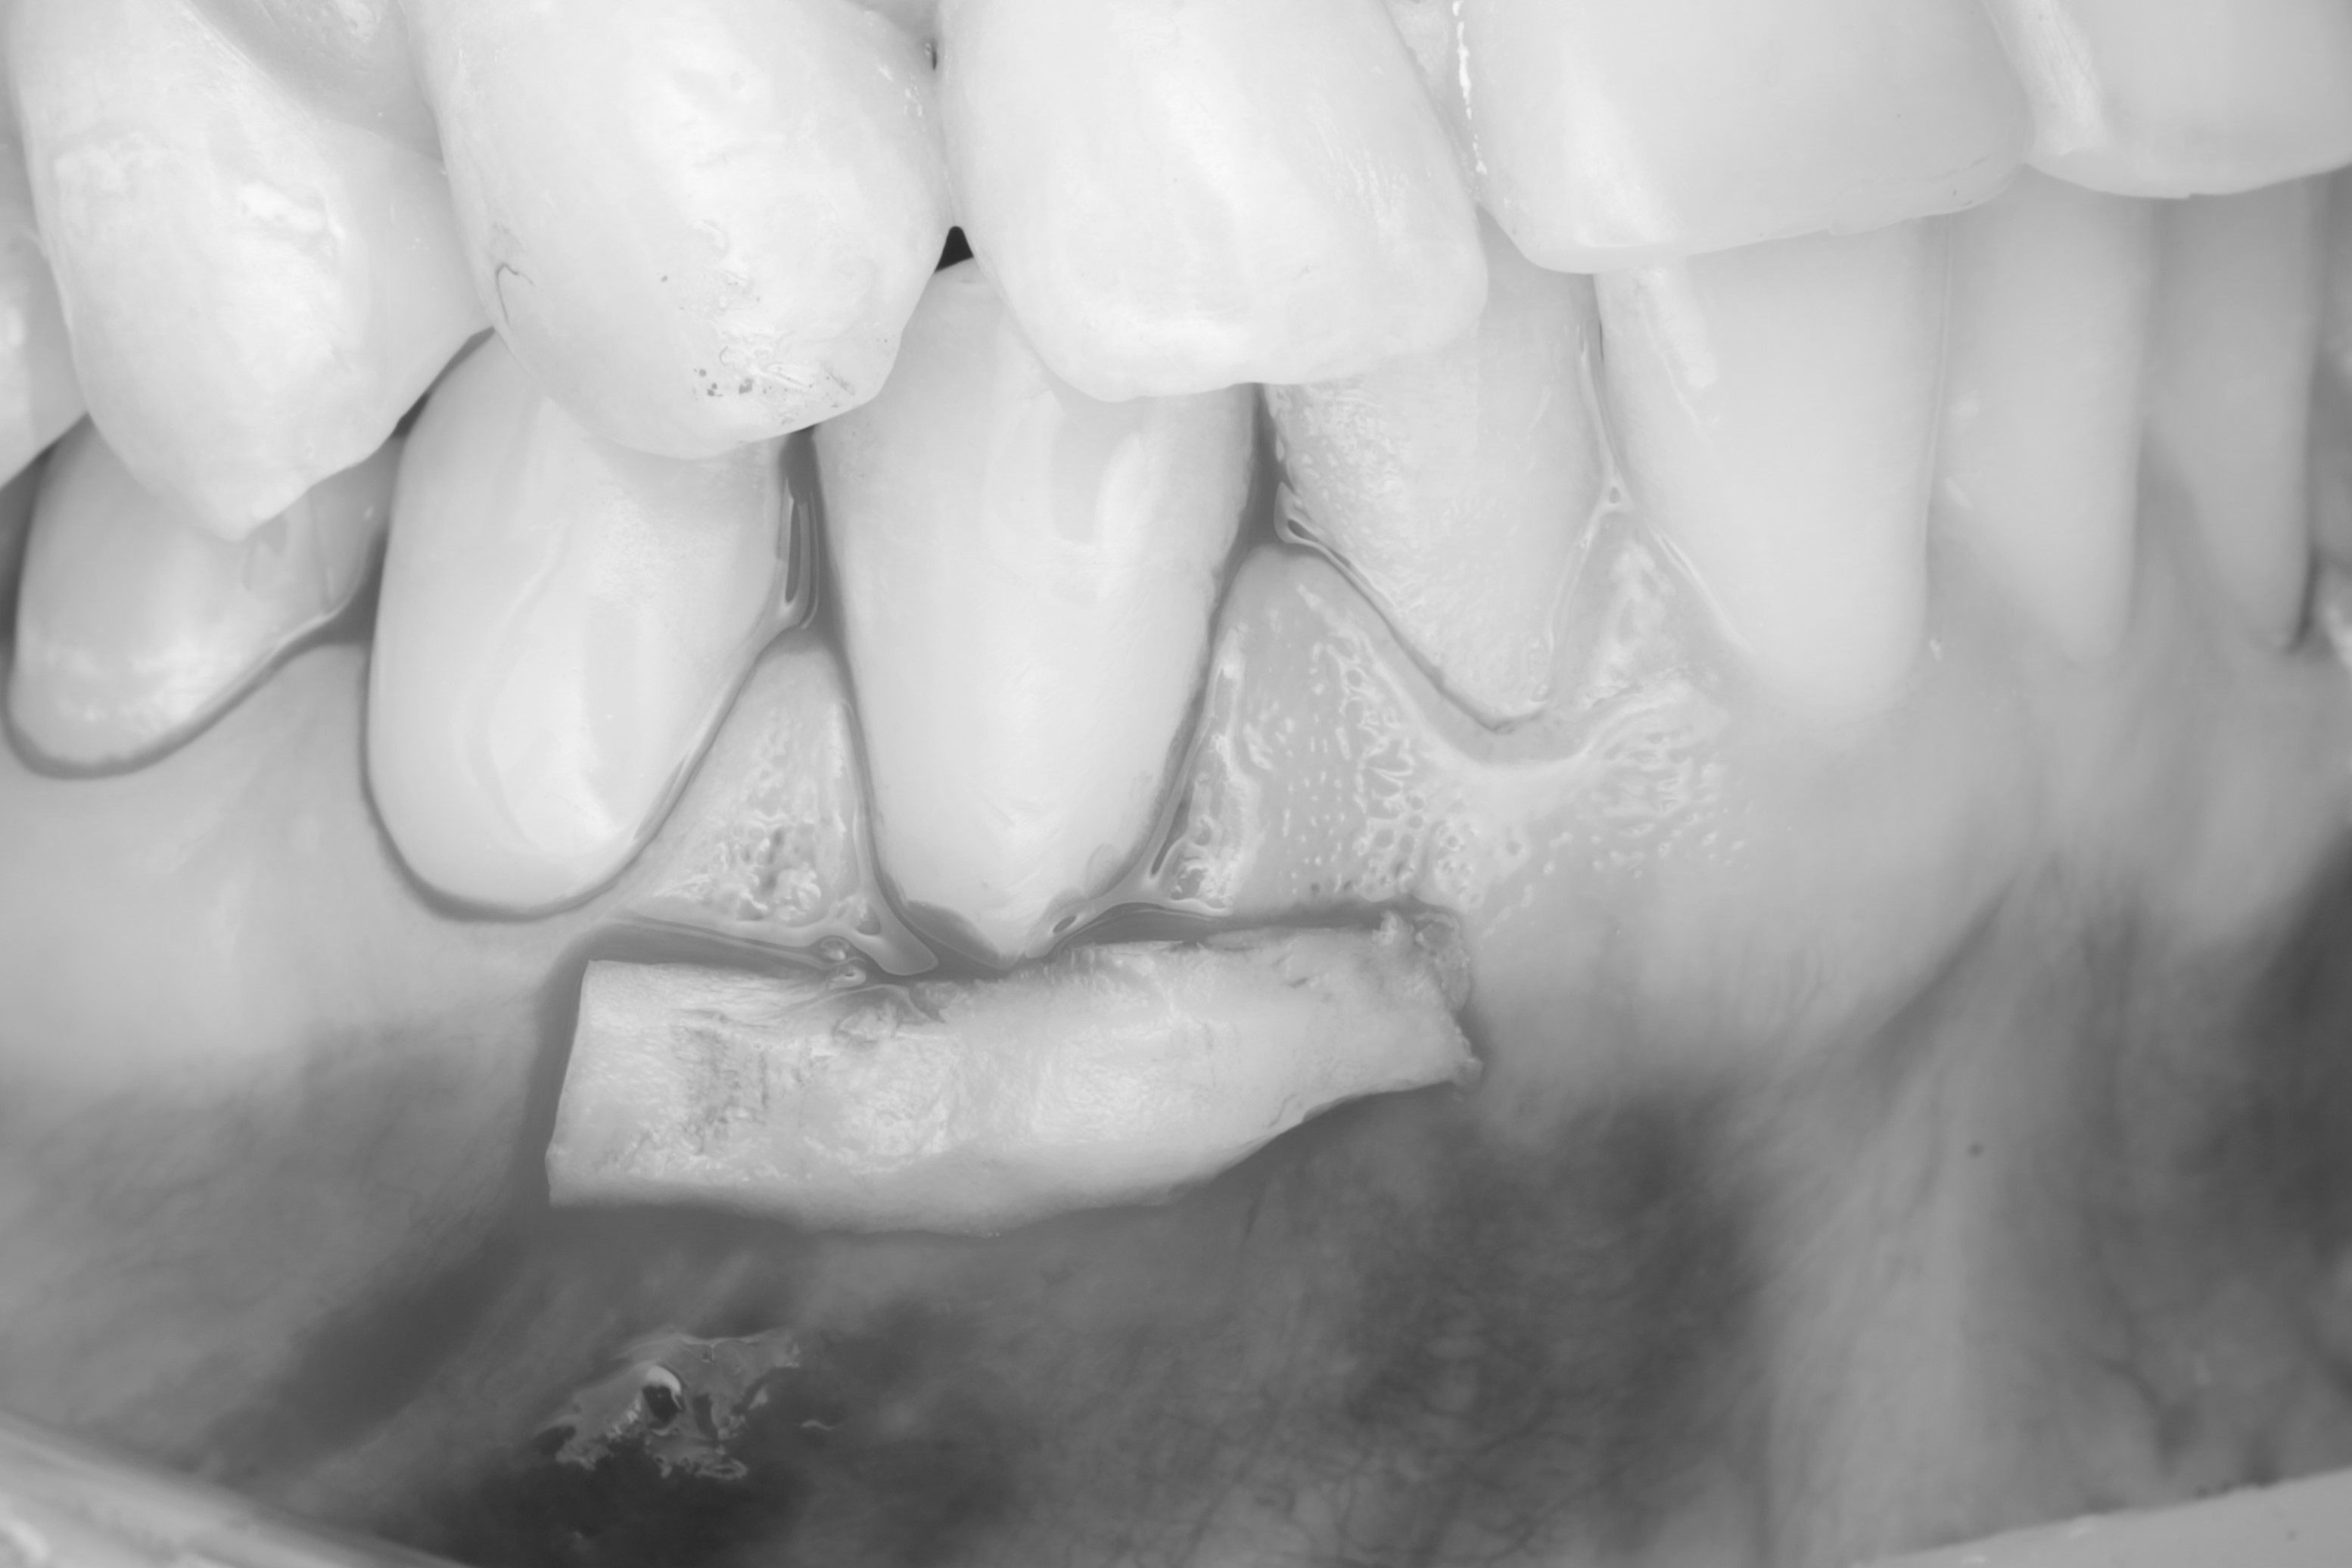

Спустя месяц пациентка с уже санированной полостью рта была направлена на закрытие рецессий. Терапевт произвёл закрытие рецессий десны композитным материалом. Также было запланировано пришлифовывание материала в полости рта и закрытие небольшой рецессии на зубе 4.4.

Операция была выполнена туннельной техникой с получением десневого трансплантата с нёба